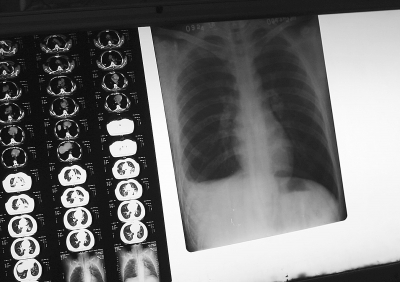

2009年3月24日,河北赵县,结核病人的X光片。

朱 斌摄